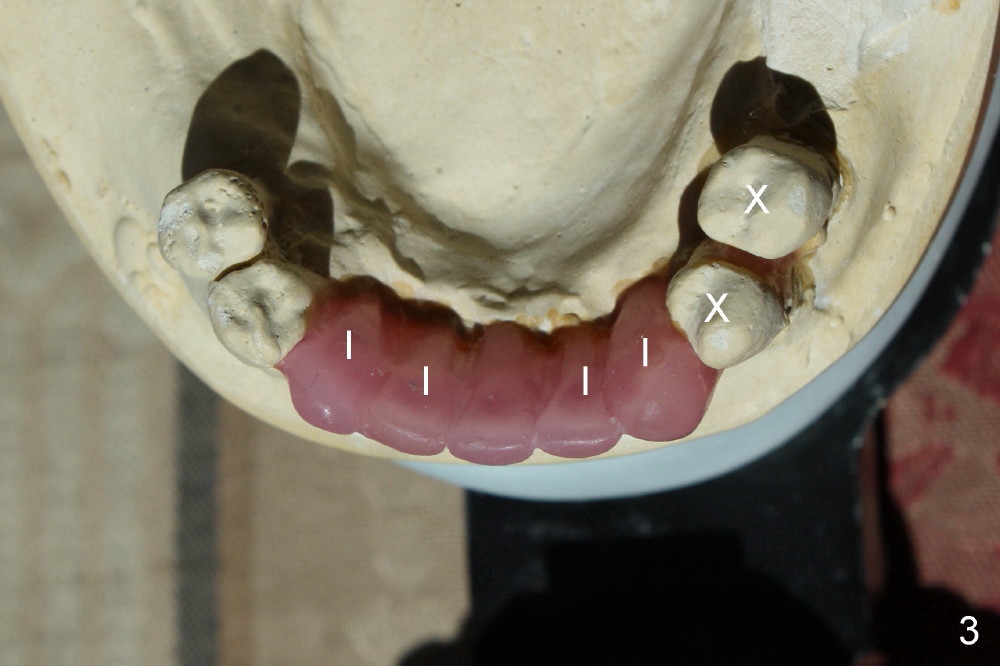

A 52-year-old man seeks treatment 2 months following loss of #22-27 fixed partial denture (FPD) (Fig.1,2). The remaining dentition has moderate to severe chronic periodontitis. Scaling & root planing has been done for the upper arch. Full mouth reconstruction is planned for the lower one in two steps. In the first procedure, the teeth #18, 20 and 21 are extracted; an incision is made from #20 to #27; two immediate implants are placed at the sites of #20,21 (one or two piece, Fig.3,5 X); another two implants at #22,27 (recently healed sites: Fig.3-5: I) and two one piece implants at lateral incisor region (I: for an implant supported FPD). In case one of the lower left premolars cannot have an implant due to proximity to the nerve, a FPD can be fabricated in the canine/premolar sextant. A splinted immediate provisional restoration will be fabricated from #20-27 immediately.